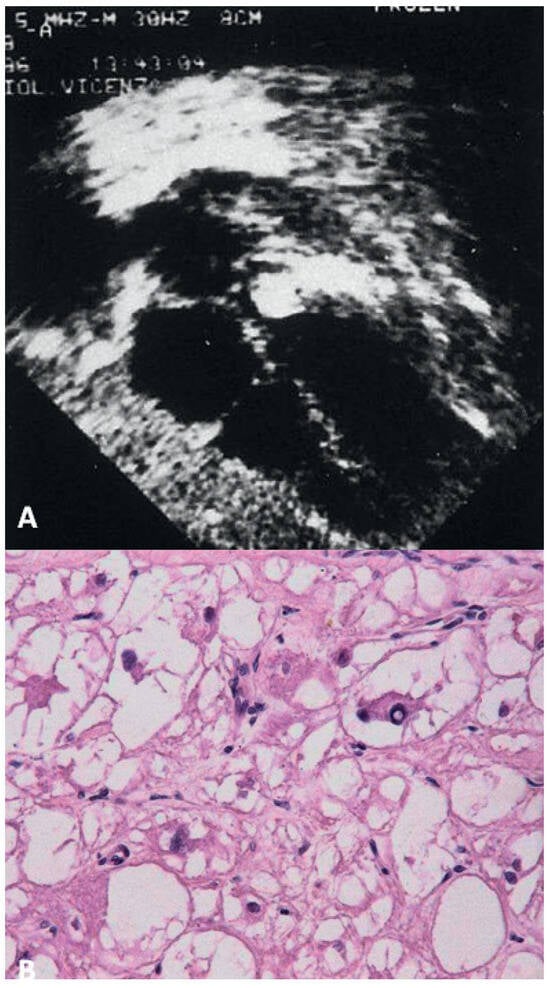

Prevalence and Pathology of Primary Cardiac Tumours

by Cristina Basso, Stefania Rizzo, Marialuisa Valente and Gaetano Thiene

Primary cardiac tumours are rare clinical observations, different from secondary neoplasms (ten times more frequent), and 90% of all primary cardiac tumours are benign. Myxoma is by far the most frequent benign tumour (75%), typically located in the left atrium, and manifests with [...] Read more.

Primary cardiac tumours are rare clinical observations, different from secondary neoplasms (ten times more frequent), and 90% of all primary cardiac tumours are benign. Myxoma is by far the most frequent benign tumour (75%), typically located in the left atrium, and manifests with intra-cavitary obstruction, embolism and constitutional symptoms, but it may also be silent and discovered incidentally by echo. Papillary fibroelastoma is a tumour usually arising on the valvular or mural endocardium, which, although quite small, may become symptomatic through embolic e vents. Typical tumours of the paediatric age group are fibroma, rhabdomyoma and teratoma. Primary malignant neoplasms account for 10% of all primary cardiac tumours and are represented by sarcomas (angiosarcoma, leiomyosarcoma, fibrosarcoma, liposarcoma, rhabdomyosarcoma undifferentiated pleomorphic sarcomas) and primary lymphomas. They usually infiltrate the cardiac walls, but may be also solely intra-cavitary, mimicking myxoma. Non neoplastic masses may consist of thrombi and infections, which again can be identified by a thorough surgical pathology examination. Cardiac non invasive imaging through transthoracic and transesophageal echocardiography easily detects heart masses. Cardiac magnetic resonance imaging a nd computed tomography are helpful complementary investigations, for refining diagnosis and in the post-surgery follow-up. Histology with immuno-histochemistry of any cardiac mass is mandatory for diagnosis, therapy and prognosis. Endomyocardial biopsy m ay be of help for histological investigation without thoracotomy particularly in right sided masses. Full article